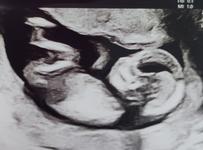

Po dnesku mame jasno😂Nase duhove babatko bude chlapcek🥰🥰 A hlavne podla rozsirenej genetiky uplne zdravy👍👍

@doda3103 Taky kamen mi dnes padol zo srdca... uplne zdravucky... lekar pozera na mna, co sono spravime este proti stresu 😂 Aj tam bolo uz vidno pipika, bez debaty 😂

@4stanka4 minule vravel lekar,ze to vyzera na dievcatko😂😂Ale teraz je to uz jasne😂

@canerko my to mame potvrdene s genetiky a teda aj na sone sa dnes ukazal, to by sa mylit nemalo 😂 Len to meno vybrat, s chlapcenskym nie som zatial stotoznena zo ziadnym, ale tak mame cas...